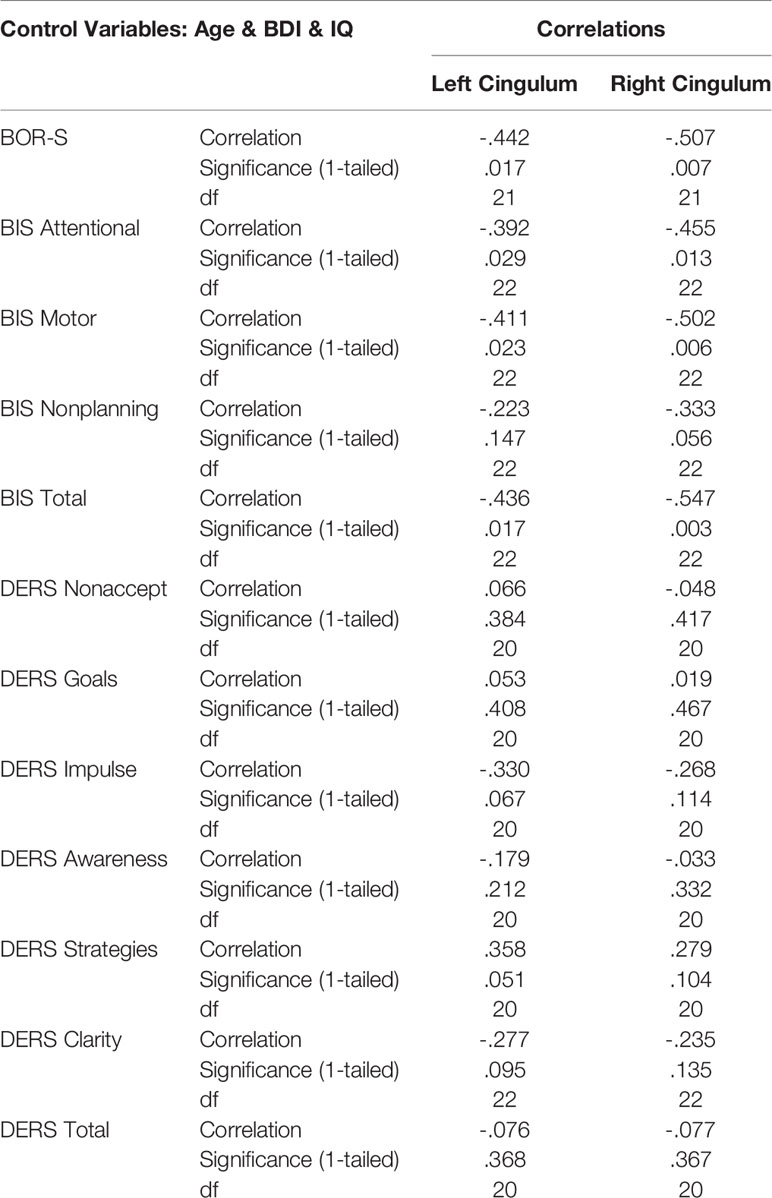

Within the NSSI group, we conducted correlations between GFA and clinical measures using partial Pearson’s correlations controlling for age and IQ. To allow our analyses to be more specific to NSSI, as opposed to depressive symptoms, we included BDI scores as covariates. We performed correlations between GFA of the right and left uncinate fasciculus and scores from the 7 DERS scales, 4 BIS scales, and the BOR-S scale from the PAI/PAI-A. Given the total of 24 comparisons and our hypothesis that higher scores on these clinical measures will be associated with lower GFA values, we used a one-tailed p-value < .002 as our level of significance. We used the same method for the right and left cingulum including using a one-tailed p-value < .002. We elected to use one-tailed p-values due to our a priori hypotheses that higher scores on clinical measures will correspond to lower GFA values.

Lower GFA of the left and right uncinate fasciculus was associated with higher total scores on the attentional subscale of the BIS. A correlation matrix can be found in Table 2, which includes comparisons that were significant at an uncorrected p < .05. For the left and right cingulum, there were no significant associations with measures of self-regulation (DERS and BIS). A correlation matrix can be found in Table 3. Finally, lower GFA of the left cingulum was associated with a longer duration of NSSI. There were no significant correlations between other severity indices (e.g., average number of episodes) and GFA. These in addition to results from other comparisons can be found in the correlation matrix in Table 4.

We also found that longer duration of NSSI was associated with lower GFA within the left and right cingulum. Because we controlled for current age in these analyses, this finding suggests that the impaired white matter integrity of this region among those with NSSI may be the result of a cumulative effect over time. However, it is also important to consider the high likelihood that any existing psychopathology had developed concurrently, or had already existed, around the time of first NSSI episode. Although some studies have reported null findings regarding differences in FA of the cingulum between psychiatric samples and controls (48, 49), a meta-analysis of adolescents with major depressive disorder (MDD) found that overall, those with depression had decreased FA within this region (50). Our finding highlights the importance of early intervention and the utility it may have in preventing aberrant, or restoring normal, neurodevelopmental trajectories. Further, given the number of functions in which the cingulum plays a role, including emotion processing, pain, and executive functioning (18), it is imperative that there is continued investigation into this possible disruption as it may lead to entrenchment of maladaptive behaviors and poorer prognosis.